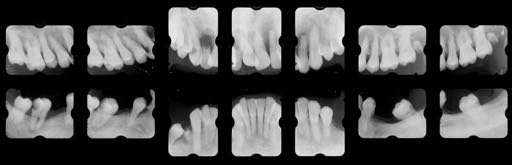

治療前

Zero Base Conceptsに基づく診断上の難易度

Degree of Difficulty +++

非常に治療難易度の高いケースである